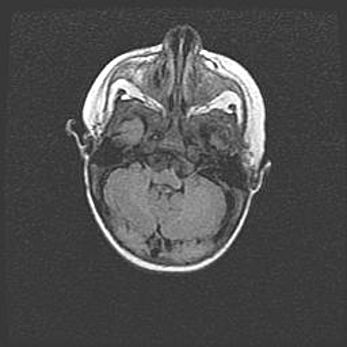

Церебральная ишемия II.

Возраст: 5 дней

Вес: 3400 г

Пол: женский

Окружность головы: 35 см

Срок гестации: 39 недель

Церебральная ишемия – это заболевание, характеризующееся недостаточностью (гипоксией) либо полным прекращением (аноксией) снабжения мозга кислородом по причине закупорки одного или нескольких сосудов. Это приводит к  что метаболическим расстройствам различной степени тяжести в тканях головного мозга, развитию коагуляционных некрозов и гибели нейронов.